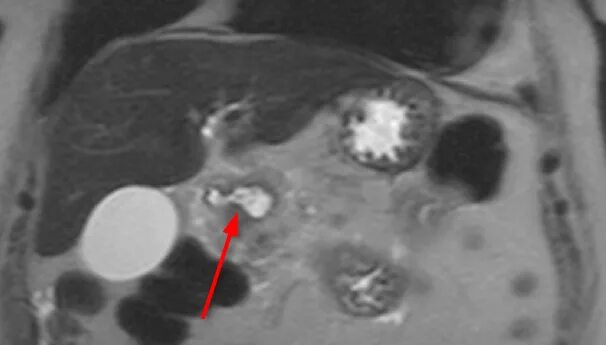

Язва желудка кт